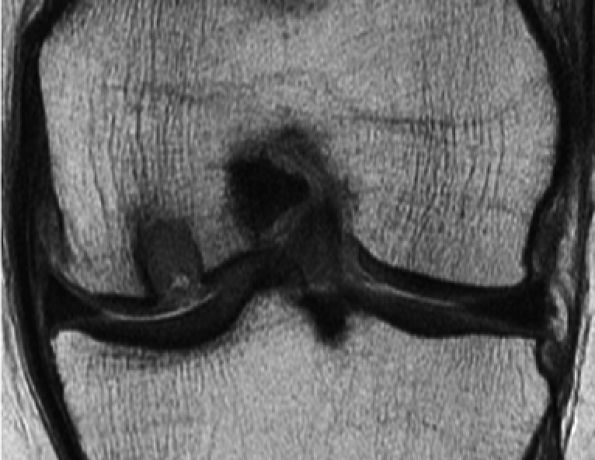

FIGURE 7.18 ● Prospective MR evaluation of a bone bruise in the knee of a 28-year-old man with a complete ACL tear. Sagittal fat-suppressed (A) and fast spin-echo (B) MR images obtained at the time of injury demonstrate characteristic bone marrow edema with compression of cartilage over the lateral femoral condyle (white arrow). A sagittal MR image obtained 19 months later (C) demonstrates proud subchondral bone with focal cartilage loss over the condyle (black arrow), as well as flap formation over the tibial plateau (arrowhead). (Reprinted by permission of SAGE Publications, Inc., from Am J Sports Med, in press.)

|